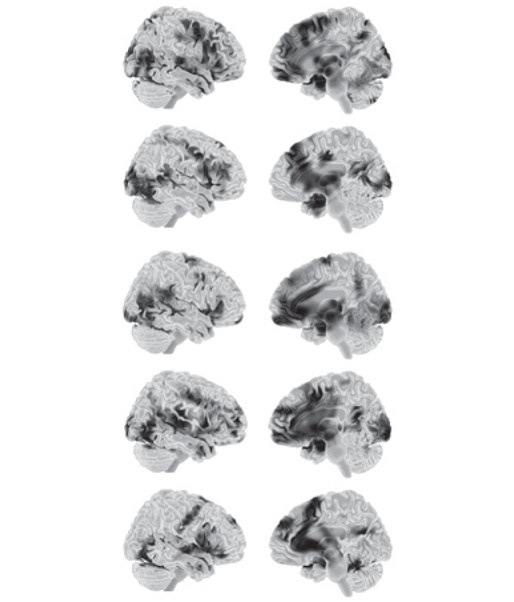

Наш проект с метаанализом продолжается, и к настоящему моменту мы собрали почти четыреста томографических исследований мозга. Для этих данных мы с коллегами применили анализ классификации (глава 1), чтобы создать пять суммарных сводок для категорий эмоций, показанных на рис. Г.2. Во всех пяти случаях значительную роль играет интероцептивная система. Все пять раз также присутствовала управляющая система, но для счастья и печали — менее четко. Помните, что вы здесь смотрите не нейронные «отпечатки», а просто абстрактные сводки. Ни один отдельный случай гнева, отвращения, страха, счастья или печали не выглядит в точности так, как соответствующая сводка. Каждый случай может использовать различные сочетания нейронов, как мы знаем из принципа вырожденности. Для каждого отдельного исследования в метаанализе, скажем, гнева, активность мозга была ближе к сводке для гнева, чем к другим сводкам, поэтому он был идентифицирован как гнев. Соответственно, мы можем диагностировать случай гнева, но мы не можем определить, какие именно нейроны будут активны. Другими словами, мы применили дарвиновский принцип популяционного мышления к конструированию гнева. Тот же самый результат получался для остальных четырех изученных нами категорий эмоций [692].

Рис. Г.2. Статистические сводки для следующих понятий (сверху вниз): «гнев», «отвращение», «страх», «счастье» и «печаль». Это не нейронные «отпечатки» (см. главу 1). Слева вид сбоку, справа — медиальный